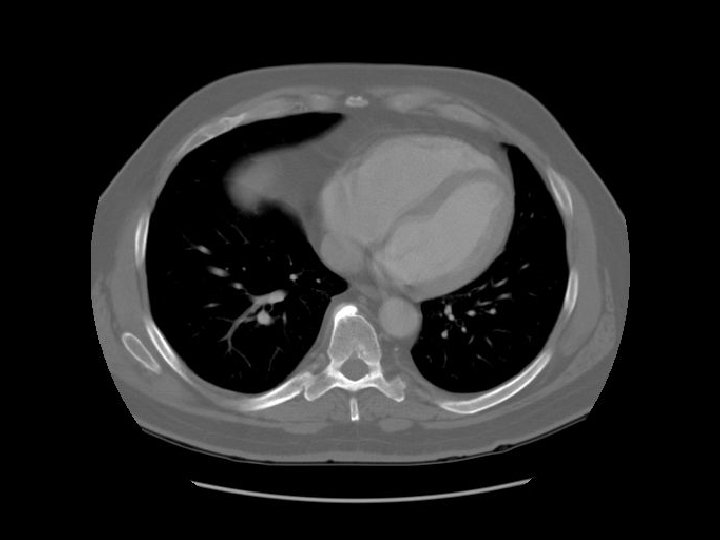

Ascending aorta Main pulmonary artery Descending aorta

Left pulmonary artery Carina

Right pulmonary artery Main pulmonary artery RUL bronchus Left pulmonary artery